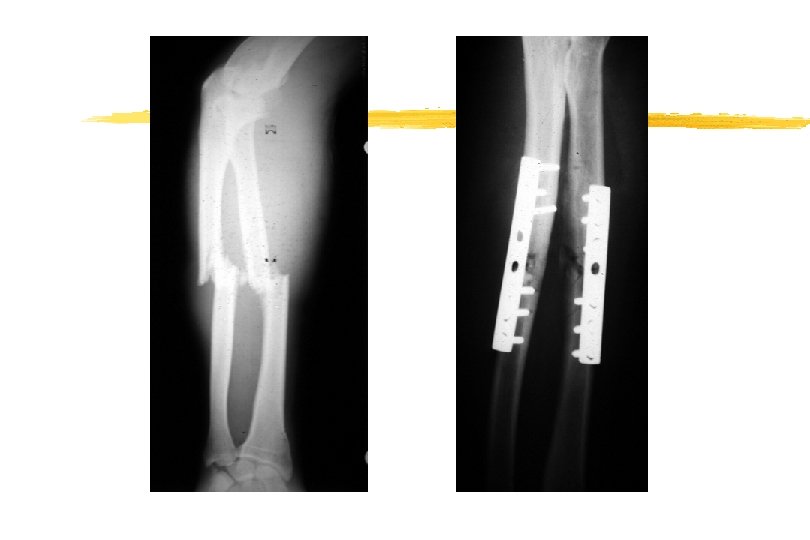

DIFFERENT TYPES OF RIGID FRACTURE FIXATION

TREATING THE FRACTURE II z How are we going to hold the reduction? x. Semi-rigid (Plaster) x. Rigid (Internal fixation) y. What treatment plan will we follow? x. When can the patient load the injured limb? x. When can the patient be allowed to move the joints? x. How long will we have to immobilise the fracture for?